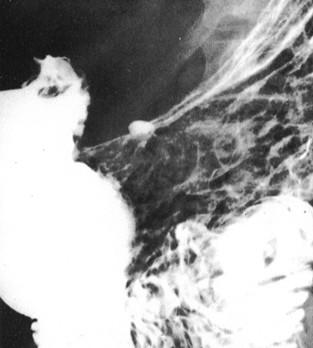

. La TOGD en double de contrast ( baryt + air +

hypotonie medicamentuese ) peut evite la superposition du

duodenum et du grele sur estomac et ce qui augemente

detection detaillee de la muqueuse gastrique et les niches de face de

l'estoma . Cette methode essentiellement utilisee pour estoma et le

colon , et rarement sur l'intestin grele .

| TOGD de estomac normale en

double de contrast |

Ulcere de la petite courbure en double de

contrast |

Images en double de contrast

d'une ulcere du paroi posterieure de estomac . |